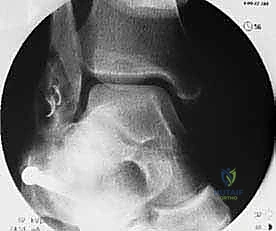

التشريح الدقيق للكاحل: فهم بنية الأربطة الجانبية

لفهم طبيعة الإجراء الجراحي، يجب أولاً فهم التشريح المعقد للكاحل. يتكون مفصل الكاحل من التقاء ثلاثة عظام: الظنبوب (القصبة)، الشظية، وعظم الكاحل (Talus). لضمان ثبات هذا المفصل أثناء الحركة، يتم دعمه بشبكة قوية من الأربطة.

الأربطة الجانبية (الموجودة في الجزء الخارجي من الكاحل) هي الأكثر عرضة للإصابة، وتتكون من ثلاثة أربطة رئيسية:

- الرباط الكاحلي الشظوي الأمامي (ATFL): هو أضعف الأربطة الجانبية والأكثر تمزقاً أثناء التواء الكاحل للداخل (Inversion).

- الرباط العقبي الشظوي (CFL): رباط قوي يساعد في استقرار الكاحل والمفصل تحت الكاحل. يتمزق عادة في الإصابات الأكثر شدة.

- الرباط الكاحلي الشظوي الخلفي (PTFL): هو الأقوى ونادراً ما يتمزق إلا في حالات الخلع الكامل للكاحل.

عندما تتمزق هذه الأربطة ولا تلتئم بشكل صحيح، تصبح رخوة وضعيفة. هذا التراخي يؤدي إلى حركة غير طبيعية لعظم الكاحل داخل المفصل، مما يسبب احتكاكاً مفرطاً وتآكلاً لغضروف المفصل بمرور الوقت.

2. التدخل الجراحي (متى يكون ضرورياً؟)

إذا استمرت الأعراض لأكثر من 3 إلى 6 أشهر رغم الالتزام التام بالعلاج التحفظي، وإذا أظهرت أشعة الرنين المغناطيسي (MRI) تمزقاً كاملاً أو تآكلاً شديداً في الأربطة، يصبح التدخل الجراحي هو الحل الوحيد لمنع تلف غضاريف الكاحل والإصابة بالخشونة المبكرة.